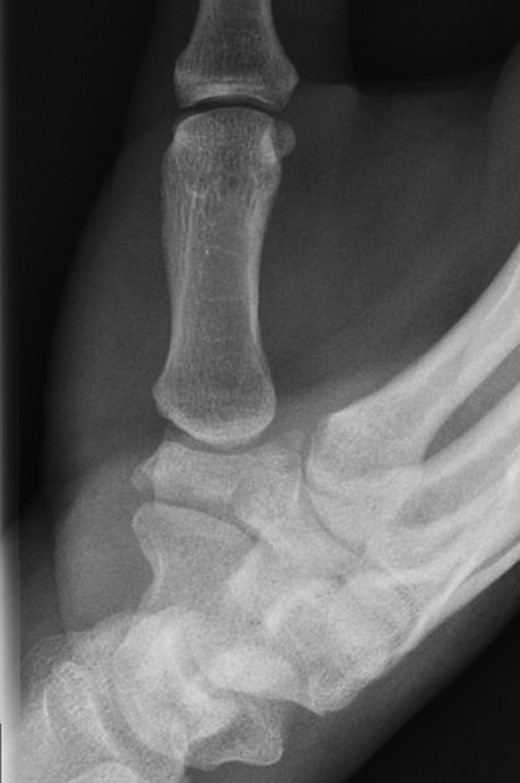

A 49-year-old man fell from his mountain bike at speed and presented to his local secondary care hospital with an injury to the base of his left thumb. There was pain and swelling at the base of the thumb with painful restriction of movements. Initial radiographs were deemed to be normal and he was treated as a soft tissue injury with a period of immobilization followed by physiotherapy. The patient was referred to us four months later as the pain and weakness were persisting. A thorough retrospective perusal of his history and imaging to date was carried out. A review of his initial plain radiographs (Fig. 1) and MRI scans indicated a fracture of the left trapezium and a CT scan was obtained to further characterize the anatomy of the fracture.